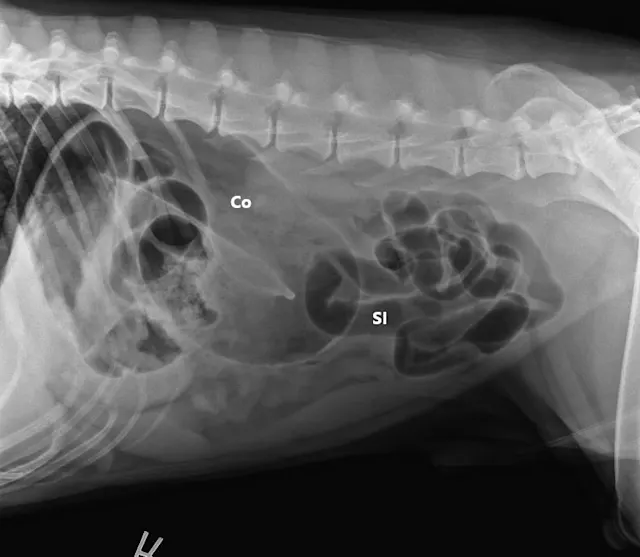

FIGURE 1A

Right lateral (A), left lateral (B), and ventrodorsal (C) abdominal radiographs demonstrating marked dilation of a single bowel loop with gas and amorphous material in the right cranial abdomen, suspected to be the colon (arrows). Caudal displacement of the small intestines (SI) can also be seen. The descending colon (Co) is poorly visualized.

Three-view abdominal radiographs revealed a single bowel loop markedly dilated with gas and amorphous material in the cranial abdomen thought to represent the colon due to its unusual position (ie, could not be tracked from caudal to cranial aspect on lateral radiograph; Figure 1). The small intestines were displaced caudally with no evidence of ileus (ie, gas filled but normal and uniform in diameter), and the descending colon was not fully visualized.